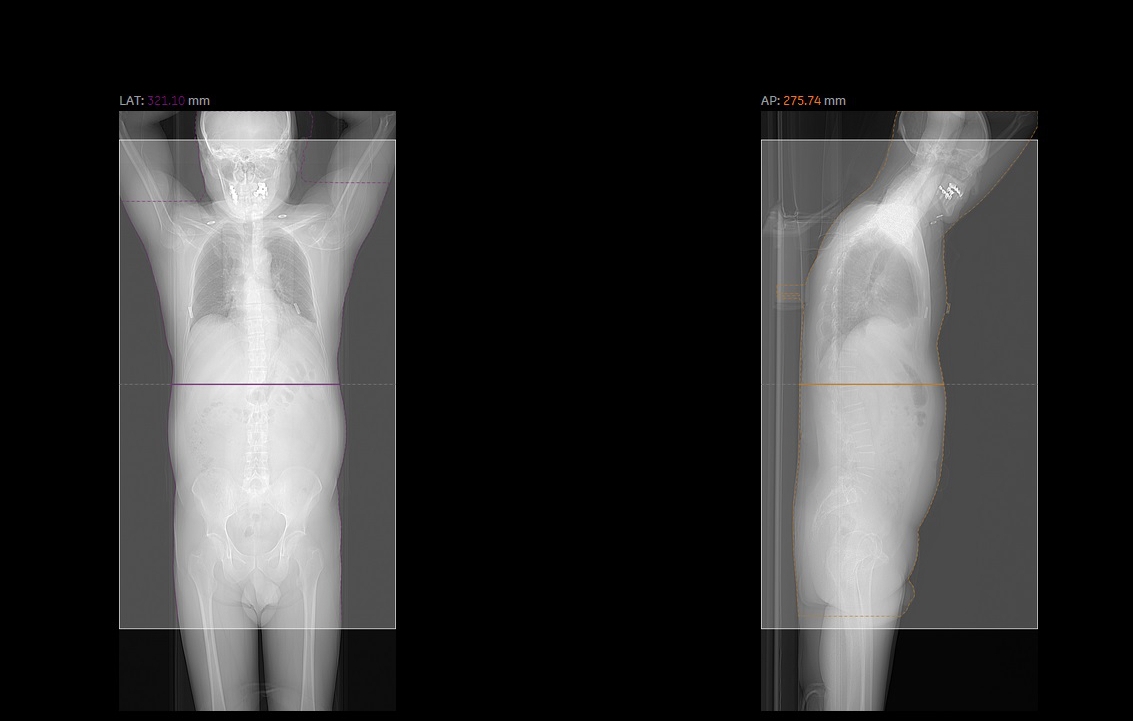

Il sistema, fornito da GE Healthcare, prevede l’invio dei dati dosimetrici direttamente da parte delle modalità diagnostiche (DACS: Dose Archiving and Communication System) ad un server dedicato, che li elabora a seconda della specifica apparecchiatura da cui provengono e li archivia per garantire analisi statistiche effettuabili in ogni momento o per la generazione di “alert” automatici al raggiungimento di dosi significative per il paziente. Ciò consente di ottimizzare l’utilizzo delle macchine secondo il principio “ALARA” (as low as reasonably achievable) che impone sempre e comunque di minimizzare la dose erogata, in particolar modo nelle pratiche speciali e verso i soggetti più sensibili, compatibilmente con la possibilità di raggiungere una diagnosi corretta e un ottimale visualizzazione delle immagini radiologiche.

«I benefici per l’utenza – spiega il dott. Salvatore Giuffrida, direttore generale dell’Azienda Cannizzaro – sono significativi innanzitutto in termini di sicurezza, perché gli operatori sono informati in tempo reale in caso di esposizioni radiogene elevate, ma anche in termini di efficienza nell’utilizzo delle apparecchiature e ottimizzazione dei protocolli, al fine di raggiungere il migliore rapporto tra elevata qualità di immagine necessaria alla diagnosi clinica e più bassa dose possibile al paziente. In termini di appropriatezza, poi, monitorare la dose consente di scegliere il percorso di indagine diagnostica più appropriato per ciascun paziente, anche in funzione della sua storia di esposizione: ad esempio – aggiunge Giuffrida – un paziente che ha già effettuato molti esami TC potrà essere indagato con altri sistemi di diagnostica».

Già oggi, l’Azienda Cannizzaro rispetta l’obbligo di riportare nel referto diagnostico relativo alle procedure medico-radiologiche l’informazione relativa all’esposizione connessa alla prestazione, che potrà essere utilizzata anche in altre Strutture e potrà essere riportata nella cartella sanitaria personale informatizzata. Nell’immediato futuro, l’ampliamento del server di gestione consentirà di includere nel “Dose Watch” il rimanente parco delle apparecchiature dell’azienda e migliorare la puntualità dell’informazione anche in termini di dose agli organi, in caso di necessità.